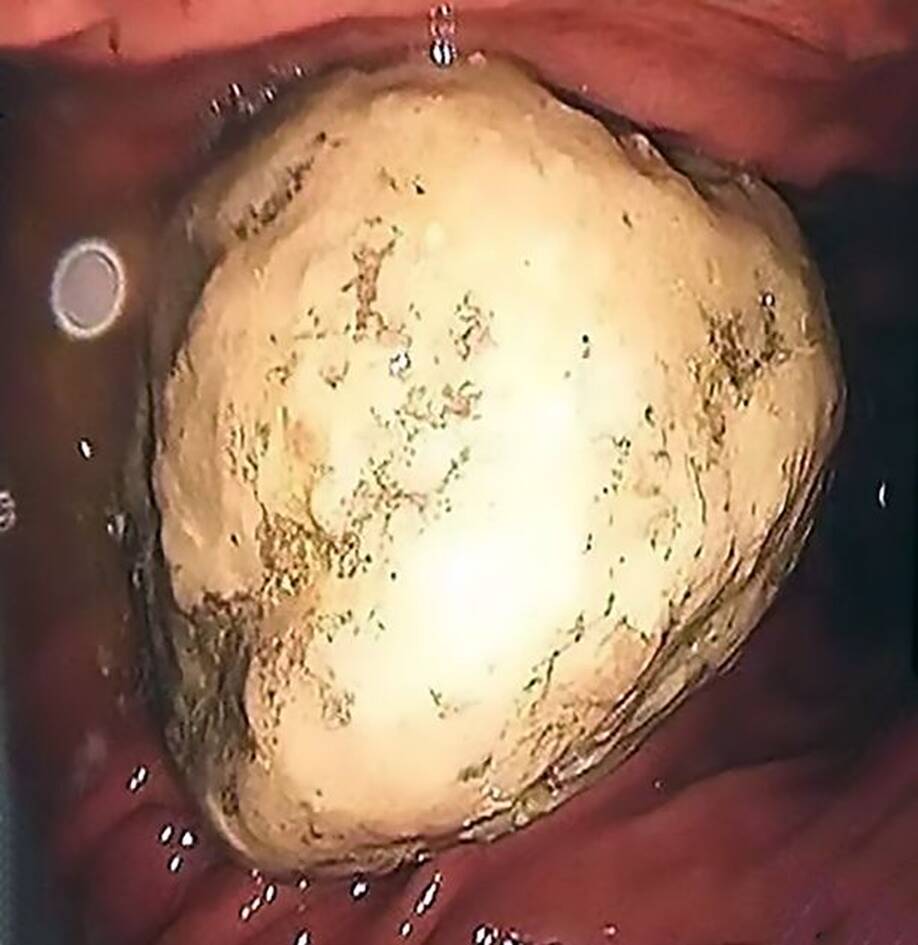

αφαίρεσαν μια πέτρα 5 εκατοστών. Πώς σχηματίστηκε; Η γυναίκα τρεφόταν με καβούρια και φρούτα με αποτέλεσμα η πρωτεΐνη και οι τανίνες να δημιουργήσουν αυτήν την πέτρα!

Μπροστά σε ένα τεράστιο σοκ βρέθηκαν οι γιατροί μόλις άνοιξαν το στομάχι μιας 40χρονης. Έτσι αποφάσισαν να την βάλουν στο χειρουργείο και μόλις διαπίστωσαν το πρόβλημα έμειναν με το στόμα ανοιχτό.